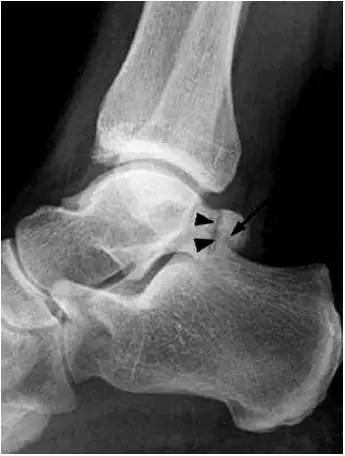

- 放射学表现主要为胫骨前下缘与距骨颈部前上缘鸟嘴样骨刺形成。

放射学表现主要为胫骨前下缘与距骨颈部前上缘鸟嘴样骨刺形成

- Ⅰ度:滑膜撞击,X线片显示有炎性反应,骨刺大小为3mm;

- Ⅱ度:骨软骨反应性骨赘>3mm;

- Ⅲ度:严重的外生骨赘,可伴有或不伴有碎裂, 在距骨背侧可见继发性骨赘,常伴有骨赘的碎裂;

- Ⅳ度:距骨和胫骨关节骨性关节炎改变。